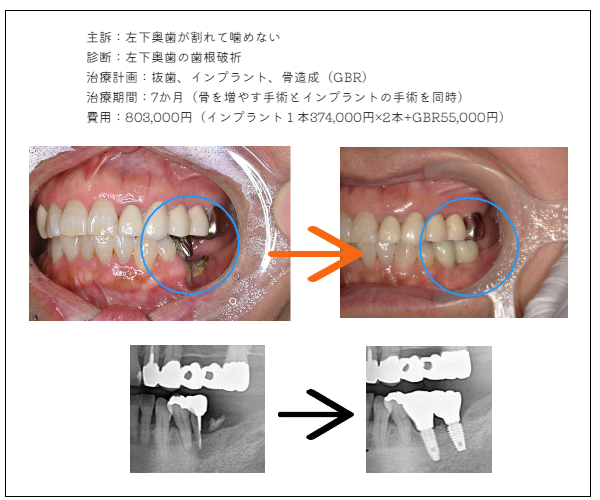

imprant症例1